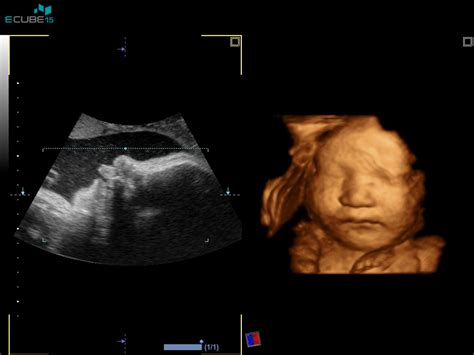

Plod namreč še vedno uspe v celoti posneti na eno sliko, čeprav se že opazi dviganje in spuščanje prsnega koša, kar nakazuje razvoj pljuč. Dihalne poti so napolnjene z amnijsko tekočino. Slika 2 prikazuje 3D-sliko celotnega ploda v gibanju, ki počasi pridobiva na telesni teži, vse več je podkožnega maščevja, ki novorojenčku pomaga uravnavati telesno temperaturo. Slika 3 ponazori, da bo plod do poroda pridobil še okoli tri kilograme. Slika 4 prikazuje žile v plodovih možganih, ki jih je mogoče s posebnimi ultrazvočnimi metodami preučevati za oceno stanja ploda.

Ultrazvok v 19. tednu nosečnosti: Preverjanje razvoja in potencialno razkritje spola

Ultrazvok v 19. tednu nosečnosti je pogosto ključen pregled, še posebej, če ni bil opravljen v preteklem tednu. Zdravnik bo pozorno spremljal otrokovo velikost, njegov razvoj in vas pomiril, da se razvija tako, kot se mora. "V 19. tednu vas čaka »le« ultrazvok, če ga še niste opravili v prejšnjem tednu." Med tem pregledom je mogoče preveriti številne vidike razvoja ploda, vključno z delovanjem vitalnih organov, kot so srce, možgani in hrbtenica.

Kadar je otrok pravilno obrnjen in si starši želijo izvedeti spol otroka pred rojstvom, je 19. teden pogosto pravi čas za to. "Ko bo dojenček pravilno obrnjen in boste želeli vedeti otrokov spol še pred rojstvom, je za to zdaj pravi čas." Večina staršev nestrpno pričakuje to informacijo, vendar to ni edina razburljiva podrobnost, ki jo lahko izveste med ultrazvočnim pregledom.